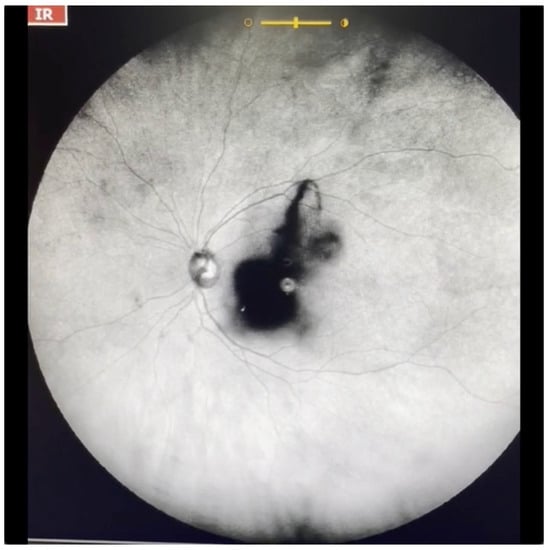

Figure 10.

Ultra-widefield IRcSLO image of an eye with Grade 5 vitreous floaters secondary to vitreous hemorrhage in a patient with history of central retinal vein occlusion that was treated with laser photocoagulation. Dense shadows are observed within the macular area in the primary gaze. See also Video S10.